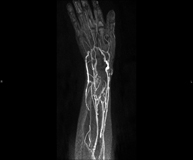

Prueba diagnóstica no invasiva que consiste en el estudio del patrón de drenaje de las venas pulmonares mediante el empleo de un campo electromagnético y ondas de radio (con un emisor y un receptor) y de contraste paramagnético (Gadolinio). No utiliza radiación ionizante. Está indicada como mapa angiográfico previo en pacientes que van a ser sometidos a ablación de las venas pulmonares, así como en su seguimiento para descartar la aparición de estenosis. - Angio-RM extremidades superiores

Prueba diagnóstica no invasiva que consiste en el estudio de las arterias de la cintura escapular, brazo, antebrazo y mano obteniendo imágenes de alta definición anatómica mediante el empleo de un campo electromagnético y ondas de radio (con un emisor y un receptor). Es indispensable el uso de contraste intravenoso paramagnético (gadolinio). Sin embargo, no utiliza radiación ionizante. La calidad de las imágenes permite realizar reconstrucciones en 2D y 3D. Está especialmente indicado en aquellos pacientes en los que hay sospecha de enfermedad vascular de ambas extremidades, en pacientes con enfermedad vascular de ambas extremidades como mapa vascular antes del tratamiento (percutáneo o quirúrgico), como mapa vascular pre-quirúrgico en pacientes con lesiones óseas o musculares que requieran cirugía…